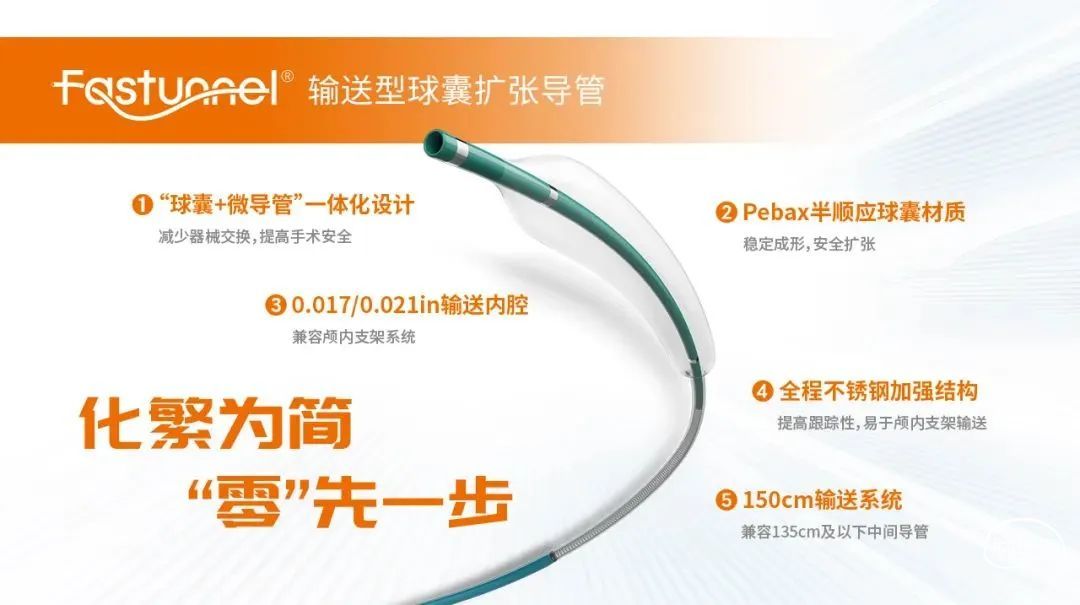

近期,解放军总医院第一医学中心王君教授团队成功应用Fastunnel®输送型球囊扩张导管(下文简称“Fastunnel®”)联合NeuroStellar® 颅内支架完成一例基底动脉重度狭窄介入治疗手术,治疗结果得到临床认可!

本例患者既往有冠脉支架置入病史,长期抗血小板+他汀二级预防,仍出现后循环梗死,发病1月内梗死有进展,一般状况较差,被动卧位,坐起后眩晕明显。术前造影提示基底动脉中下段串联重度狭窄,前循环未向基底动脉代偿供血。同时基底动脉造影远端大脑后动脉未见显影,远端导丝着陆区不良,应用长交换导丝不能走远,稳定性差。考虑使用Fastunnel®输送型球囊扩张导管,先扩张近端病变,后扩张远端病变,随后通过Fastunnel®释放NeuroStellar®颅内支架,实现“零交换”治疗颅内串联重度狭窄病变。

器械准备

21系列 2.5×10mm Fastunnel®输送型球囊扩张导管

NeuroStellar® 4.5mm*30mm颅内支架

微导丝置于右侧小脑上动脉,导引Fastunnel®通过狭窄。

沿球囊送入NeuroStellar® 4.5mm*30mm颅内支架一枚,定位准确后释放支架。